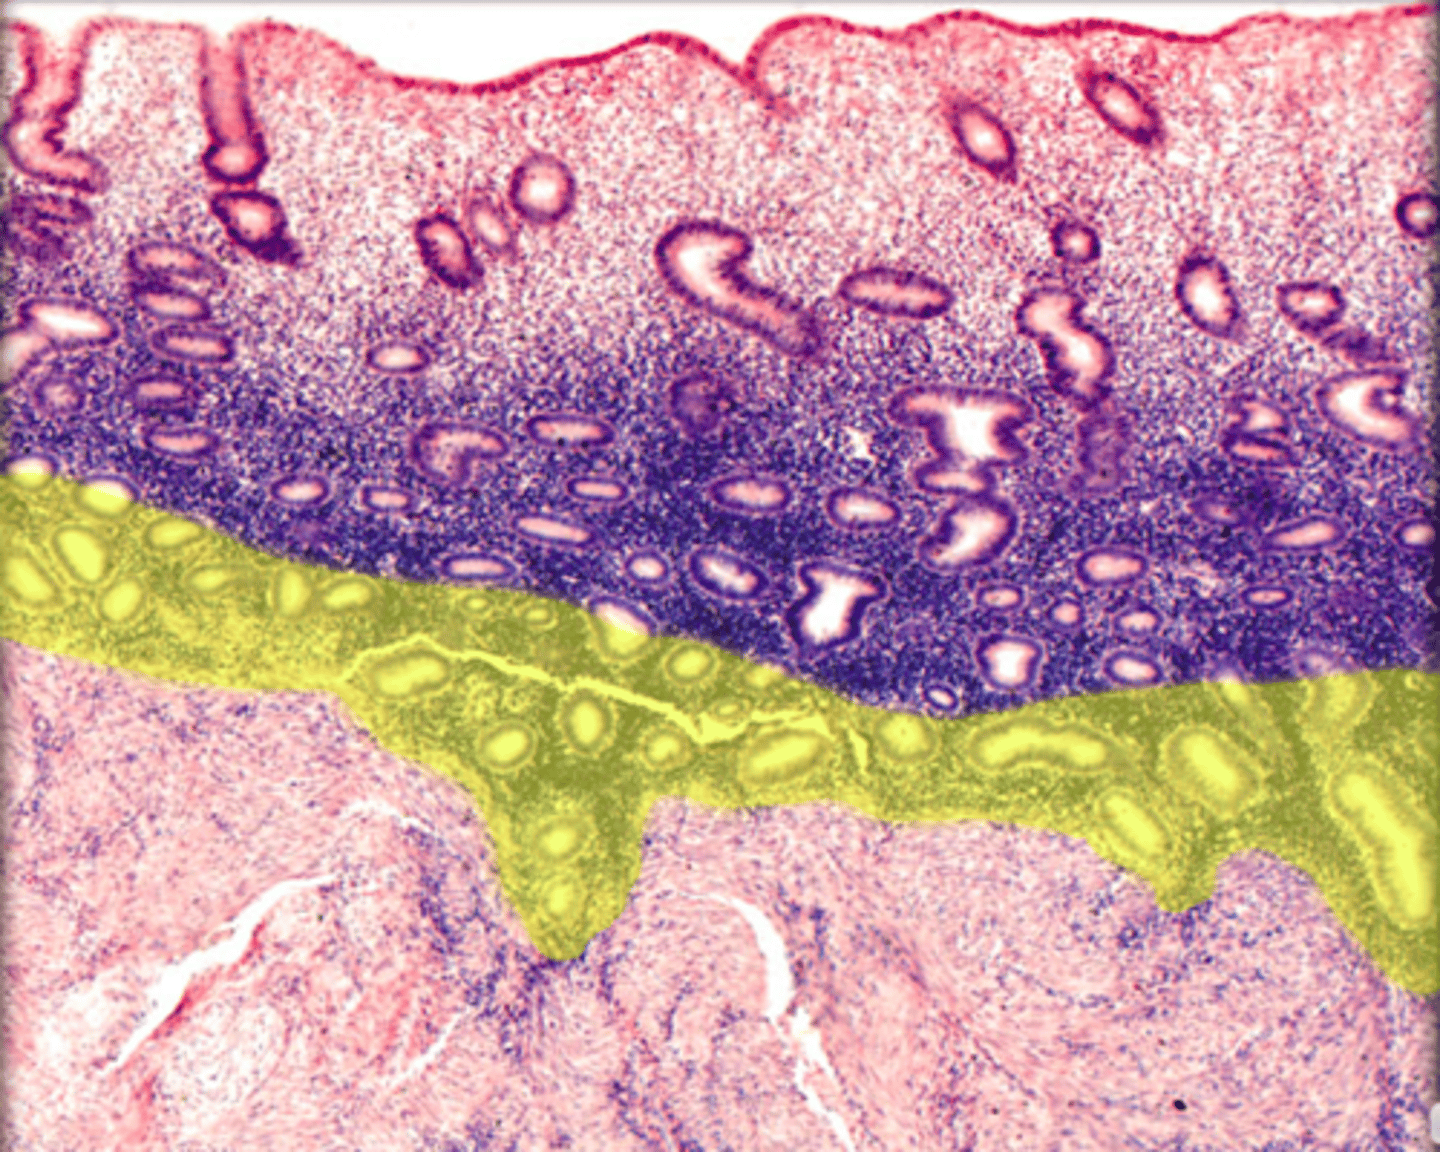

cortex

A

medulla

B

surface epithelium

tunica albuginea

2

endometrium

uterine glands

basal layer

in endometrium

functional layer

myometrium

smooth muscle

in myometrium it is made of

perimetrium

farthest layer

loose connective tissue, and simple squamous epithelium

what is perimetric made of